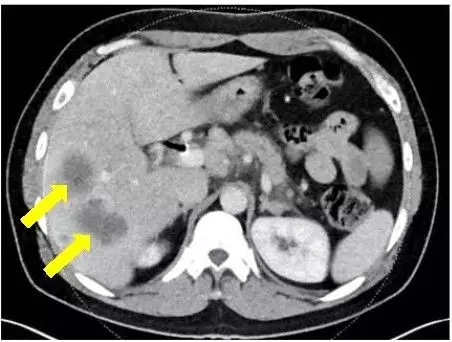

胰腺癌确诊时

FOLFIRINOX治疗5个月病灶明显缩小 vs olaparib治疗21个月病灶全部消失